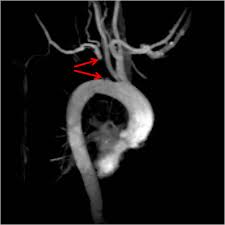

Subclavian steal syndrome is a syndrome associated with steno-occlusive pathology of the proximal subclavian artery with subsequent reversal of flow in the ipsilateral vertebral artery. It is characterized by flow reverse in the vertebral artery to supply the vascular bed distal to the occlusionobstruction and to perfuse the arm collateral flow. The subclavian steal syndrome is a rare but important cause of syncope.

The term subclavian steal describes retrograde blood flow in the vertebral artery associated with proximal ipsilateral subclavian artery stenosis or occlusion usually in the setting of subclavian artery occlusion or stenosis proximal to the origin of the vertebral artery. Subclavian artery stenosis is an uncommon vascular disease showing a 4-fold left rather than right-sided predisposition. Symptoms of SSS include vertigo during arm exertion and hand or arm pain and numbness or weakness in the arm involved due to hypoperfusion.

Subclavian steal syndrome SSS is a condition secondary to an occlusion in the proximal subclavian artery which leads to upper-extremity blood supply to be derived by reversal of flow within the ipsilateral VA. Blood is drawn from the collateral circulation which results in reversed blood flow in the ipsilateral vertebral artery. The term subclavian steal was coined by Fisher as the reversed retrograde ipsilateral vertebral blood flow was due to the stealing of blood from the posterior cerebral circulation by the subclavian artery.

Blood from the contra-lateral vertebral artery is siphoned over at the basilar junction and flows retrograde into the. Right Subclavian Steal Associated with Aberrant Right Subclavian Artery David M.